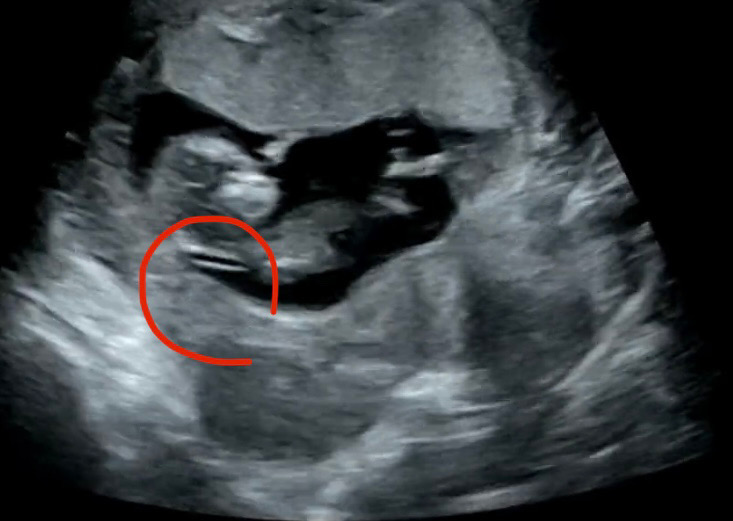

11주 6일차 아가 영상을 보다가 목투명대(?) 같은 걸 보게되었어요.. 오늘이 12주 0일인데, 구정연휴 때문인지, 예약이 밀려서인지 13주 2일차에 목투명대 검사와 니프티 검사 예약이 잡혔어요. 대부분 12주차에 목투명대 검사를 실시한다고 들었는데 저흰 다른분들보다 일주일 넘게 기다려야 해서 걱정이 많았거든요.. 어제 찍은 영상 돌려보다가 목뒤에 라인이 잡혀있길래 캡쳐해봤는데 목투명대가 맞는거죠? 두께는 어때 보이시나요? ㅠ 두께가 3mm 넘으면 위험군으로 들어간던데.. 아가 몸에 비해 목투명대가 좀 두꺼워 보이는 것 같기도 하고 아닌것 같기도 하고 걱정이네요 ㅠ 고수님들 고견 좀 부탁 드릴게요 한번만 봐주세요~~ㅠ

크게 안두꺼워 보이는데요^^두꺼운건 보면 차이가 확나요

ㅎㅎ저도 지금 영상보면 헉 꽤 두꺼운데 싶은데 1.45로 통과했어요!! 너무 크게 걱정하지마세요ㅎㅎㅎ막상 재보면 얇답니당!

오우 저희 둘째랑 투명대길이 비슷해보여요 진짜 3미리가 넘어가거나 3미리면 뭔가달라보인다 하더라구요 저정도는 괜찮을꺼예요 저희 둘째도 1.27 로 넘어갔어요 너무불안해 하지마시구 맘편히기다려보셔요